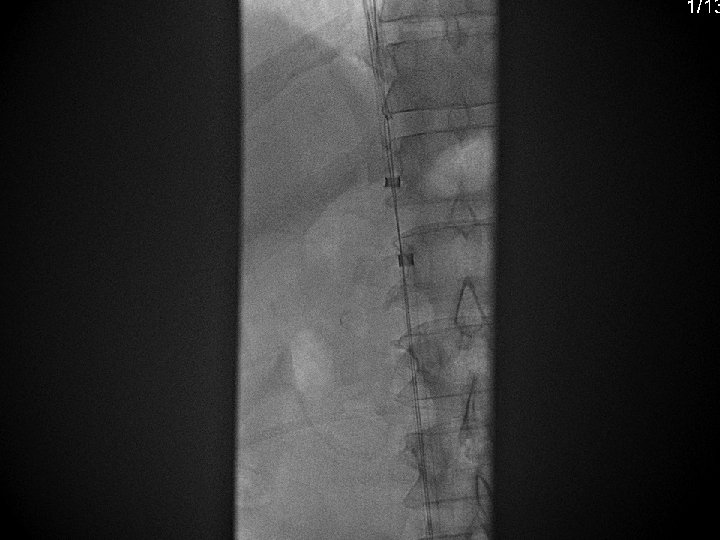

IVC Filter Removal Straight forward and Complex

Equipment Sheaths Directional catheters Directional guidewires Loop snares Grasping devices Baskets

Removal of an “Intravascular Foreign Body” Straight forward Loop snare Grasping device Complex Multiple devices used including angioplasty balloons, bronchoscopy forceps, and the“in situ” snare technique.

Retrieval with a snare and a long sheath or guiding catheter Günther Tulip (Cook) Celect (Cook) Opt Ease (Cordis Endovascular) Option (Angiotech) G 2 X, Eclipse, Meridian (Bard)

Retrieval with a “grasping”device Recovery Filter, G 2 (Bard Peripheral Vascular) Aln (Aln Implants)